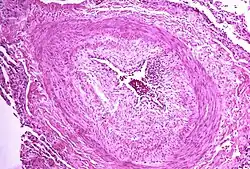

.jpg)

The pathogenesis of pulmonary arterial hypertension (WHO Group I) involves the narrowing of blood vessels connected to and within the lungs. This makes it harder for the heart to pump blood through the lungs, as it is much harder to make water flow through a narrow pipe as opposed to a wide one. Over time, the affected blood vessels become stiffer and thicker, in a process known as fibrosis. The mechanisms involved in this narrowing process include vasoconstriction, thrombosis, and vascular remodeling (excessive cellular proliferation, fibrosis, and reduced apoptosis/programmed cell death in the vessel walls, caused by inflammation, disordered metabolism and dysregulation of certain growth factors).[27][28] This further increases the blood pressure within the lungs and impairs their blood flow. In common with other types of pulmonary hypertension, these changes result in an increased workload for the right side of the heart.[16][29] The right ventricle is normally part of a low pressure system, with systolic ventricular pressures that are lower than those that the left ventricle normally encounters. As such, the right ventricle cannot cope as well with higher pressures, and although right ventricular adaptations (hypertrophy and increased contractility of the heart muscle) initially help to preserve stroke volume, ultimately these compensatory mechanisms are insufficient; the right ventricular muscle cannot get enough oxygen to meet its needs and right heart failure follows.[16][28][29] As the blood flowing through the lungs decreases, the left side of the heart receives less blood. This blood may also carry less oxygen than normal. Therefore, it becomes harder and harder for the left side of the heart to supply sufficient oxygen to the rest of the body, especially during physical activity.[30][31][11] During the end-systolic volume phase of the cardiac cycle, the Gaussian curvature and the mean curvature of the right ventricular endocardial wall of PH patients were found to be significantly different as compared to controls.[32]